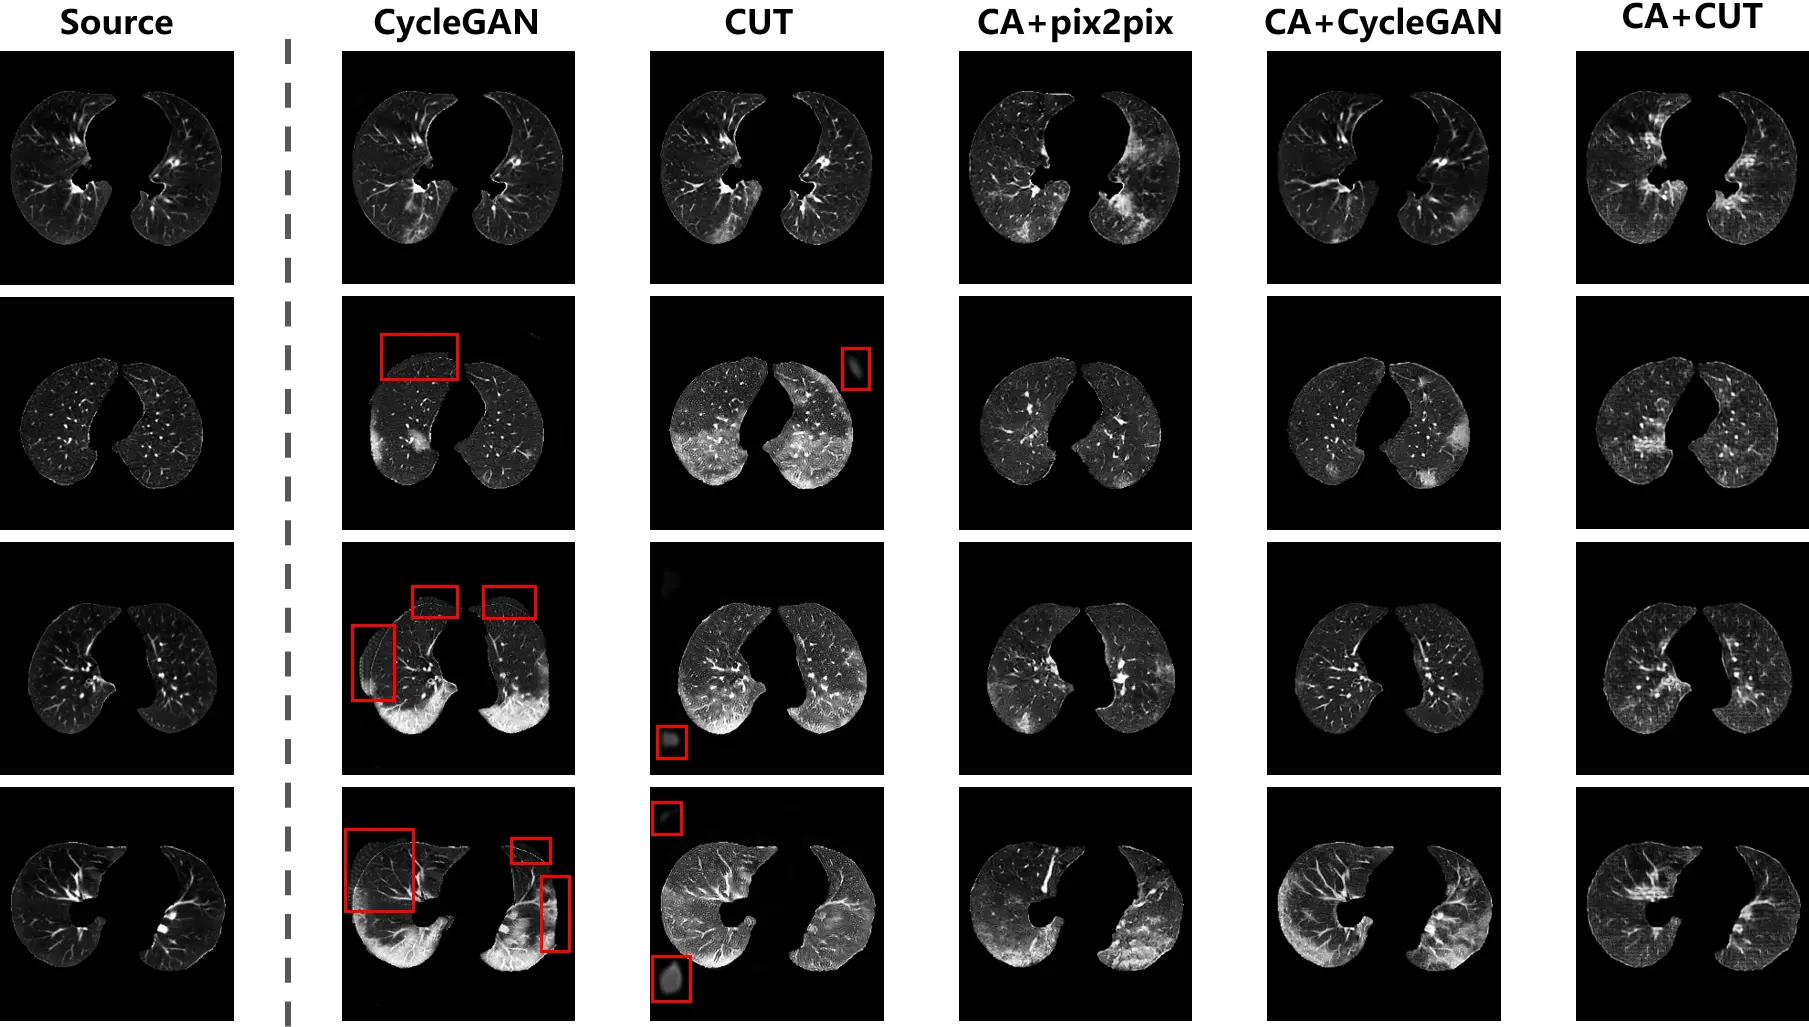

CycleGAN and CUT were implemented using both types of training data, while pix2pix was able to be executed using the paired data collected by content adaptation. The synthesis outputs are exhibited in Figure 9. As shown in the second and third columns, the distribution bias in training samples leads to hallucinations (highlighted in red boxes) in the background of the outputs. Similar to the phenomenon in Figure 5 and Figure 6, the translation models attempted to match the outputs to target samples by revamping the foreground and background. The unbiased samples provided by content adaptation enabled the translation models to focus on the desirable translation mapping, such that in the fourth to sixth columns of Figure 9 the foreground was intact and the lesions were generated. Furthermore, the bias distracted the attention of the models that the diversity of the outputs from the original data were not as good as the content adapted ones. Especially, in the third column, analogical lesion patterns were shared among the outputs of CUT.

Figure 9. The synthesis of CT scans with COVID-19 infection. The distribution bias in the original data leads to hallucinations (i.e. spurious non-anatomical artifacts or unrealistic background structures), as shown by the red boxes. The hallucination has disappeared in the outputs of the translation models trained on content adapted data.